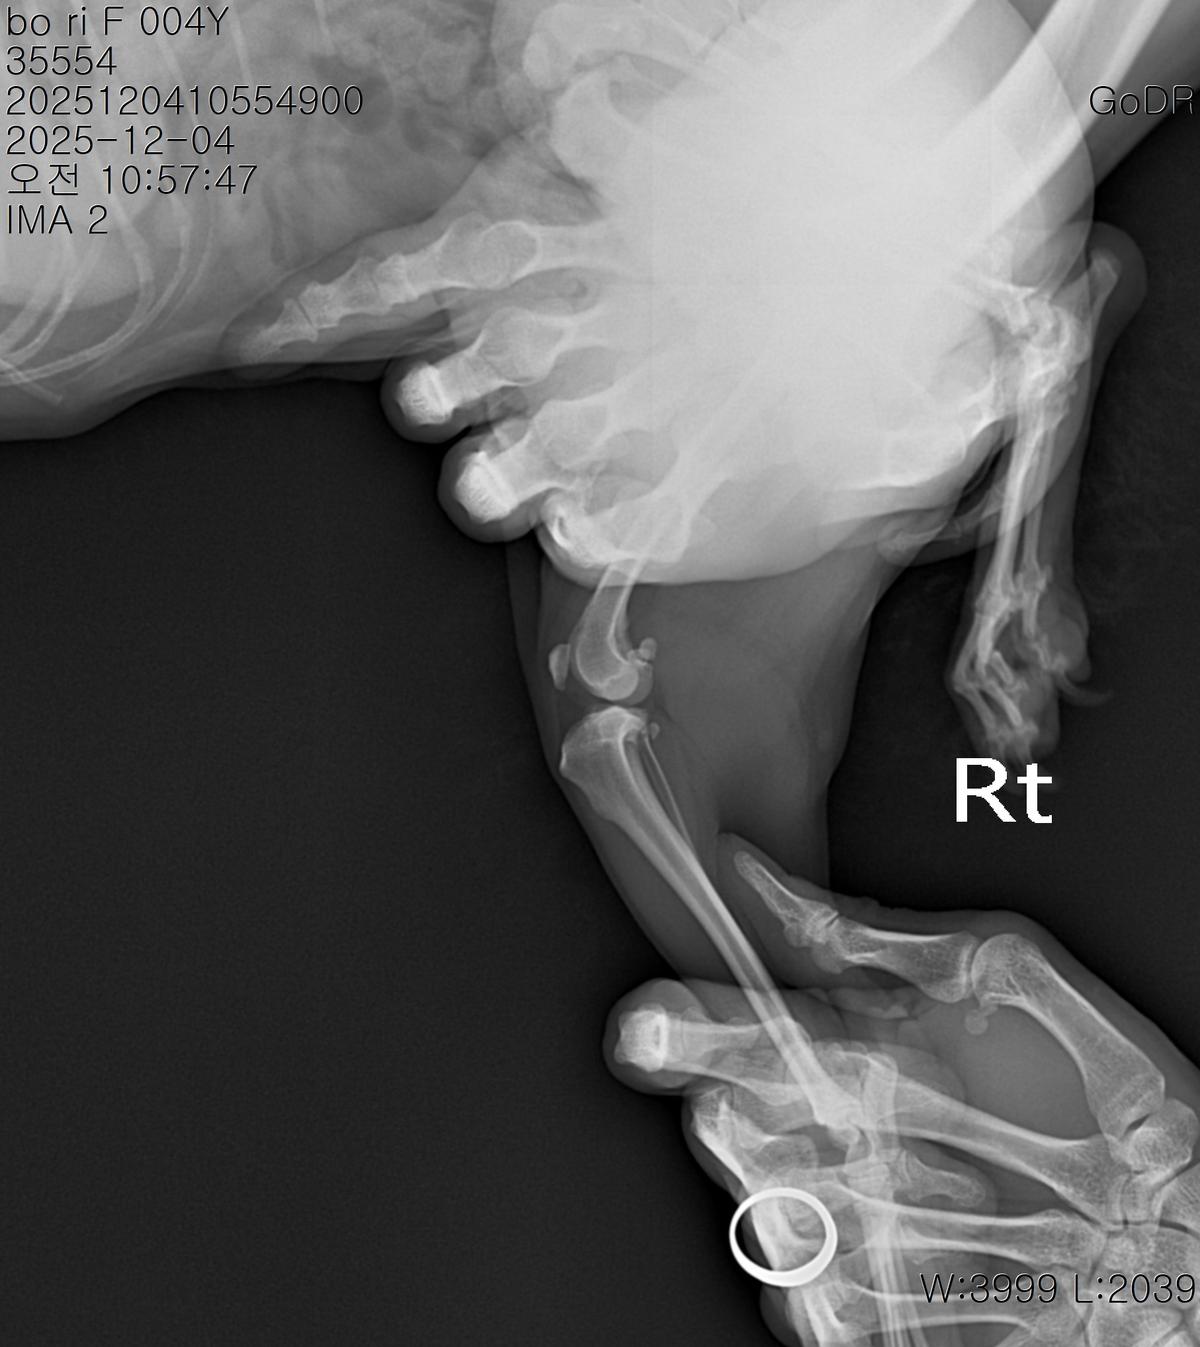

강아지 슬개골탈구 진단 받았습니다 몇군데 병원을 다녀봤는데 진단이 달라 궁금해서 질문 해봅니다 일단 저희 강아지는 오른쪽 다리를 갑자기 들고 다니고 절어 병원을 방문하게 되었고요 왼쪽은 증상이 없지만 오른쪽만 있는 상태였습니다 첫번째랑 두번째 병원에서는 슬개골 탈구 진행중이고 왼쪽이 3기 오른쪽이 2기 정도라고 했습니다 하지만 왼쪽은 아예 빠져있어 증상도 없고 아파하지도 않는다고 했고 오른쪽은 빠졌다 안빠졌다 해서 증상이 있다고 했고 십자인대가 파열된 걸론 보이지 않는다고 했습니다 그래서 양쪽 슬개골탈구 수술만 진행하면 된다고 했고요 근데 세번째 병원에서는 둘다 왼쪽이 좀 더 심한 슬개골 탈구 3기 정도라고 했고 오른쪽만 십자인대 부분파열이 보인다고 했습니다 그래서 십자인대 파열이 아닌 왼쪽은 굳이 수술할 필요가 없고 나중에 십자인대 파열이 오거나 증상이 나타나면 그때 수술하면 된다고 했습니다 그래서 오른쪽 슬개골탈구 수술과 tplo를 하는 방식으로 수술을 한다고 했습니다 여기서 궁금한점은 1. 십자인대 파열이 사진상으론 보이지 않는다고 하는데 사진상으로 알 수 있는 건가요? 2. 십자인대 파열이 아니면 슬개골탈구 수술을 굳이 할 필요 없다고 하셨는데 맞는 건가요? 3. 꼭 슬개골탈구와 십자인대 수술을 같이 해야 결과과 더 좋아지나요? 4. 사진상으로 십자인대와 슬개골 수술을 같이 해야할까요? 5. tplo 수술방법이 가장 안전하고 좋은 수술방법인가요? 6. 슬개골탈구로 인해 십자인대가 끊어지는건 아니라고 들었는데 맞나요? 슬개골 탈구 수술로 십자인대를 예방할 수 있나요?